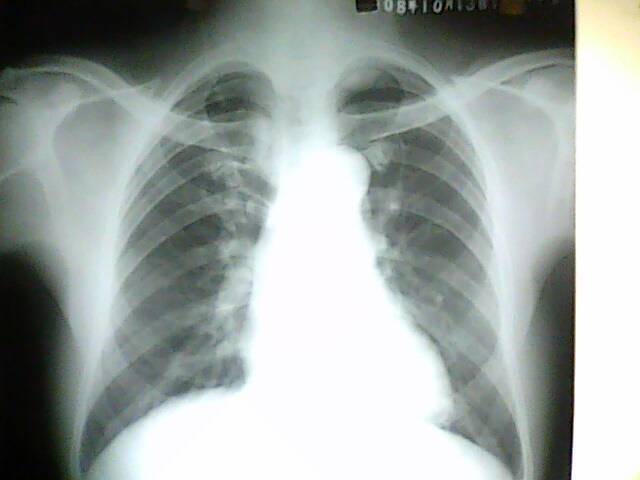

标题: X4925:胸片:男54岁。常规检查

男54岁。常规检查 。给病人透视了一下,这个位置侧位看不到。还是考虑你胸膜病变。已建议ct,有结果我会发上来。

左肺尖病灶:首先考虑肺上沟癌,其次左上纵隔肿瘤。

左上胸膜肿瘤。

没有侧位片,从正位片上可知气管未受压,考虑为来自后纵隔或胸膜的良性肿瘤.

气管似略右移,病变位于主动脉水平以上,首先排除胸内甲状腺

既然是常规检查,肯定没有临床指征,考虑肺顶胸膜局限性增厚,建议ct以除外占位。

这个病人做了ct,追踪时已经出院,没看到结果和片子。病历上写的是:ct报的是左胸廓入口占位,建议颈部和胸部增强扫描。但据说病人不愿意增强,已经出院。